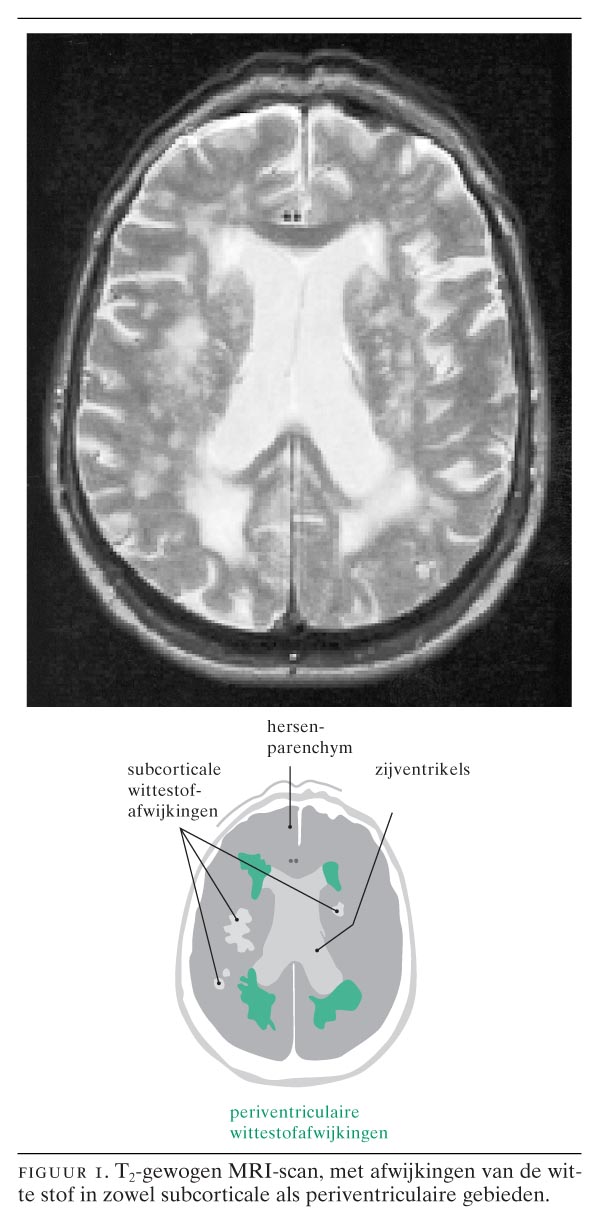

Zie onderstaande afbeelding voor verduidelijking. De hele pagina bevat namelijk teveel informatie. Per hersengebied en per patroon van vlekjes bekijken we de mogelijke oorzaken.

Op onderstaande afbeelding tonen we hoe de verschillende afwijkingen eruit kunnen zien op een scan. De zwarte stukken midden in het beeld zijn holtes in de hersenen, die ook wel ventrikels worden genoemd.